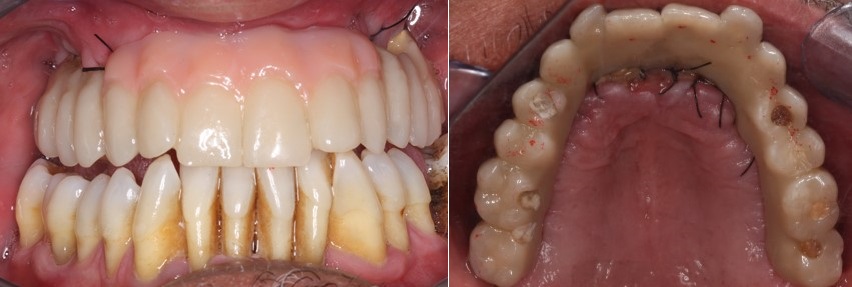

Βλέπουμε στην φωτογραφία που ακολουθεί αριστερά, τα εμφυτεύματα στην θέση των πίσω δοντιών ενώ δεξιά βλέπουμε εμφυτεύματα που τοποθετήθηκαν μετά την εξαγωγή των δοντιών κάτω από ακινητοποιημένα με σύρμα δόντια.

Στο στάδιο της τοποθέτησης των εμφυτευμάτων πήραμε ένα αποτύπωμα των εμφυτευμάτων, με το οποίο οι συνεργάτες μας στο οδοντοτεχνικό εργαστήριο κατασκεύασαν μια προσωρινή ακίνητη εργασία.

Η εργασία αυτή είχε ακριβώς τα ίδια χαρακτηριστικά με τα φυσικά δόντια, όπως φαίνεται στην επόμενη φωτογραφία. Διατήρησε την θέση των δοντιών ακόμη και τις ατέλειες τους, ώστε να φαίνεται φυσική και στηρίζονταν στα εμφυτεύματα που τοποθετήθηκαν στο πρώτο στάδιο.